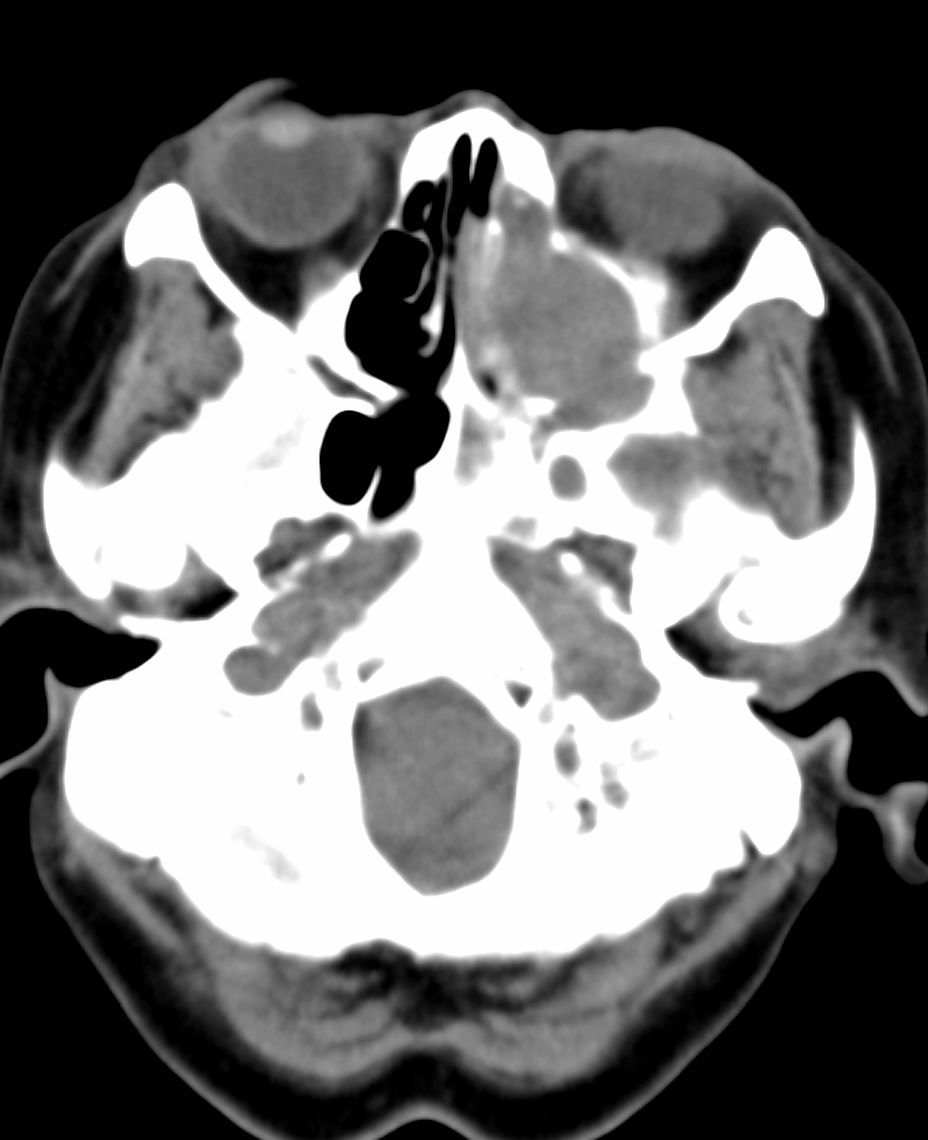

女,69岁。鼻出血2月多。(会诊病史就这样简单)鼻副窦ct检查如下:

左侧鼻腔及上颌窦见软组织块影,左侧上颌窦腔扩大,骨质吸收,右侧上颌窦见半圆形软组织密度影,鼻中隔向右侧弯曲,左侧鼻和鼻窦内翻型乳头状瘤可能性大,建议增强。

左侧上颌窦及鼻腔内见软组织密度影,其内密度不均匀,见斑片状高密度影,右侧上颌窦腔明显扩大,窦壁吸收变薄,鼻中隔右偏,右侧上颌窦见一半圆形软组织密度影,边界清楚,其内密度均匀。诊断,1、左侧鼻腔及上颌窦内翻乳头状瘤可能性大,上颌窦癌,息肉及霉菌性上颌窦炎待除外。2、右侧上颌窦粘膜下囊肿。

1)考虑左侧上颌窦内翻乳突状瘤突入左侧鼻腔。2)副鼻窦炎,右侧上颌窦黏膜下囊肿。

病理:霉菌性左侧上颌窦炎伴左侧上颌窦纤维组织增生。

窦腔密度不均匀增高,无明显钙化征象,后外侧及内侧窦壁膨胀明显,局部破坏消失,筛窦受累及,但双侧对比发现左侧窦壁骨质有硬化增白现象,这可能是支持左侧霉菌性上颌窦炎的主要依据点。